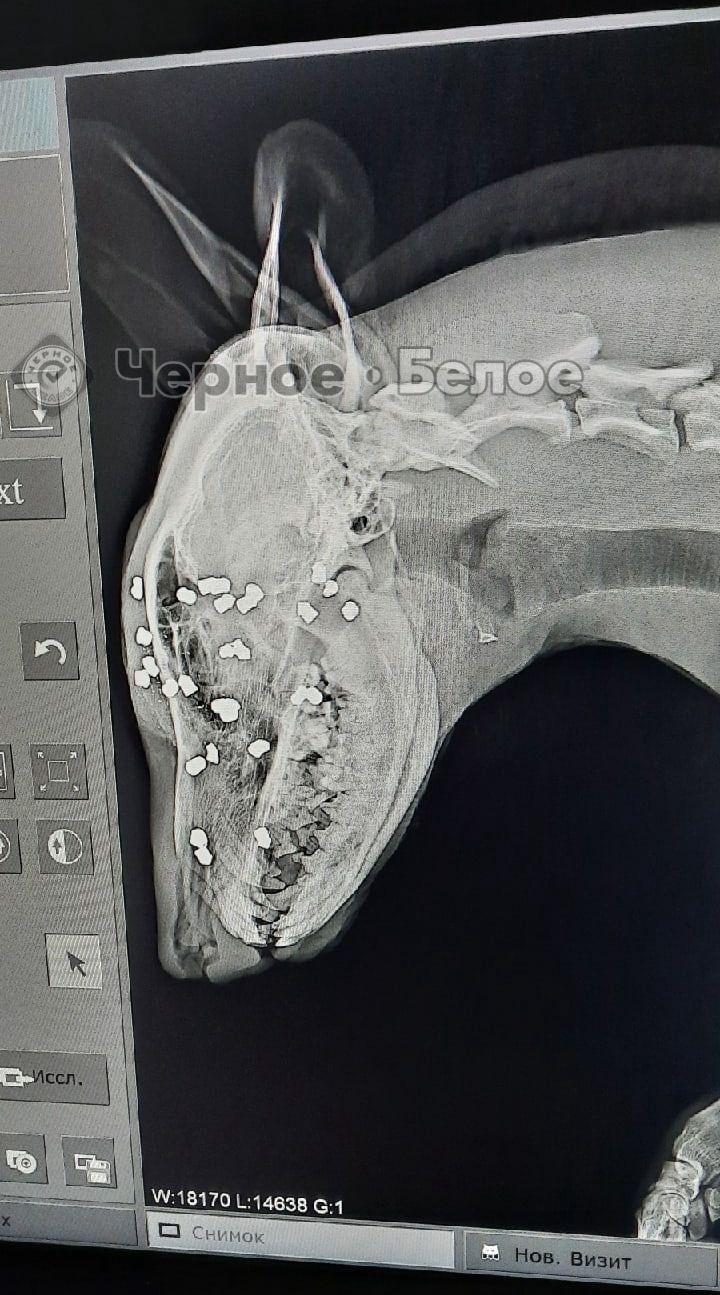

Напомним, 18 февраля братья – жители поселка Березовая роща Нагайбакского района – в окрестностях одной из ферм расстреливали бродячую собаку из пневматической винтовки. Один из братьев стрелял в пса, увязавшего в глубоком снегу, обязательно целясь в голову и в глаза, а другой снимал происходящее на видео и активно комментировал.

Зоозащитницы нашли на снегу следы крови и само место расправы. Затем девушки услышали, что со стороны одного из строений слышится жалобное скуление. Оказалось, что внутри прятался раненый пес. Айгуль и ее подруга доставили собаку в одну из ветклиник Магнитогорска. Во время операции из мягких тканей головы собаки достали около 20 пуль, также врачам пришлось удалить глазные яблоки животному.